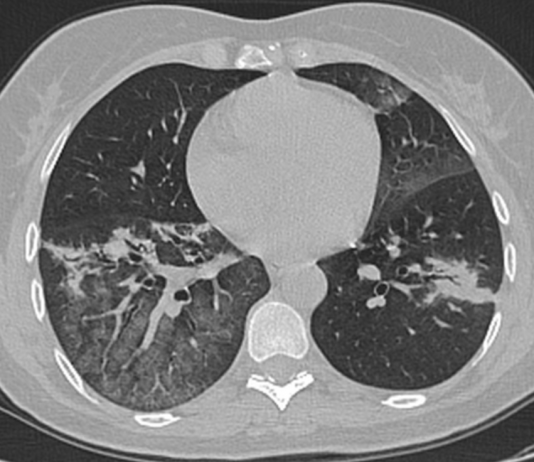

UOC Radiologia Pediatria PO G. Di Cristina ARNAS Civico Palermo

G.Paviglianiti, U.Burgio, M.Castiglia, L.Ferraro, M.Finazzo, G.Marsala, L.Putignano, A. Re. Direttore: M.Pia Pappalardo

Giunto al PS del PO G.Di Cristina di Palermo accompagnato dalla zia.

Fratello Covid + (asintomatico)...